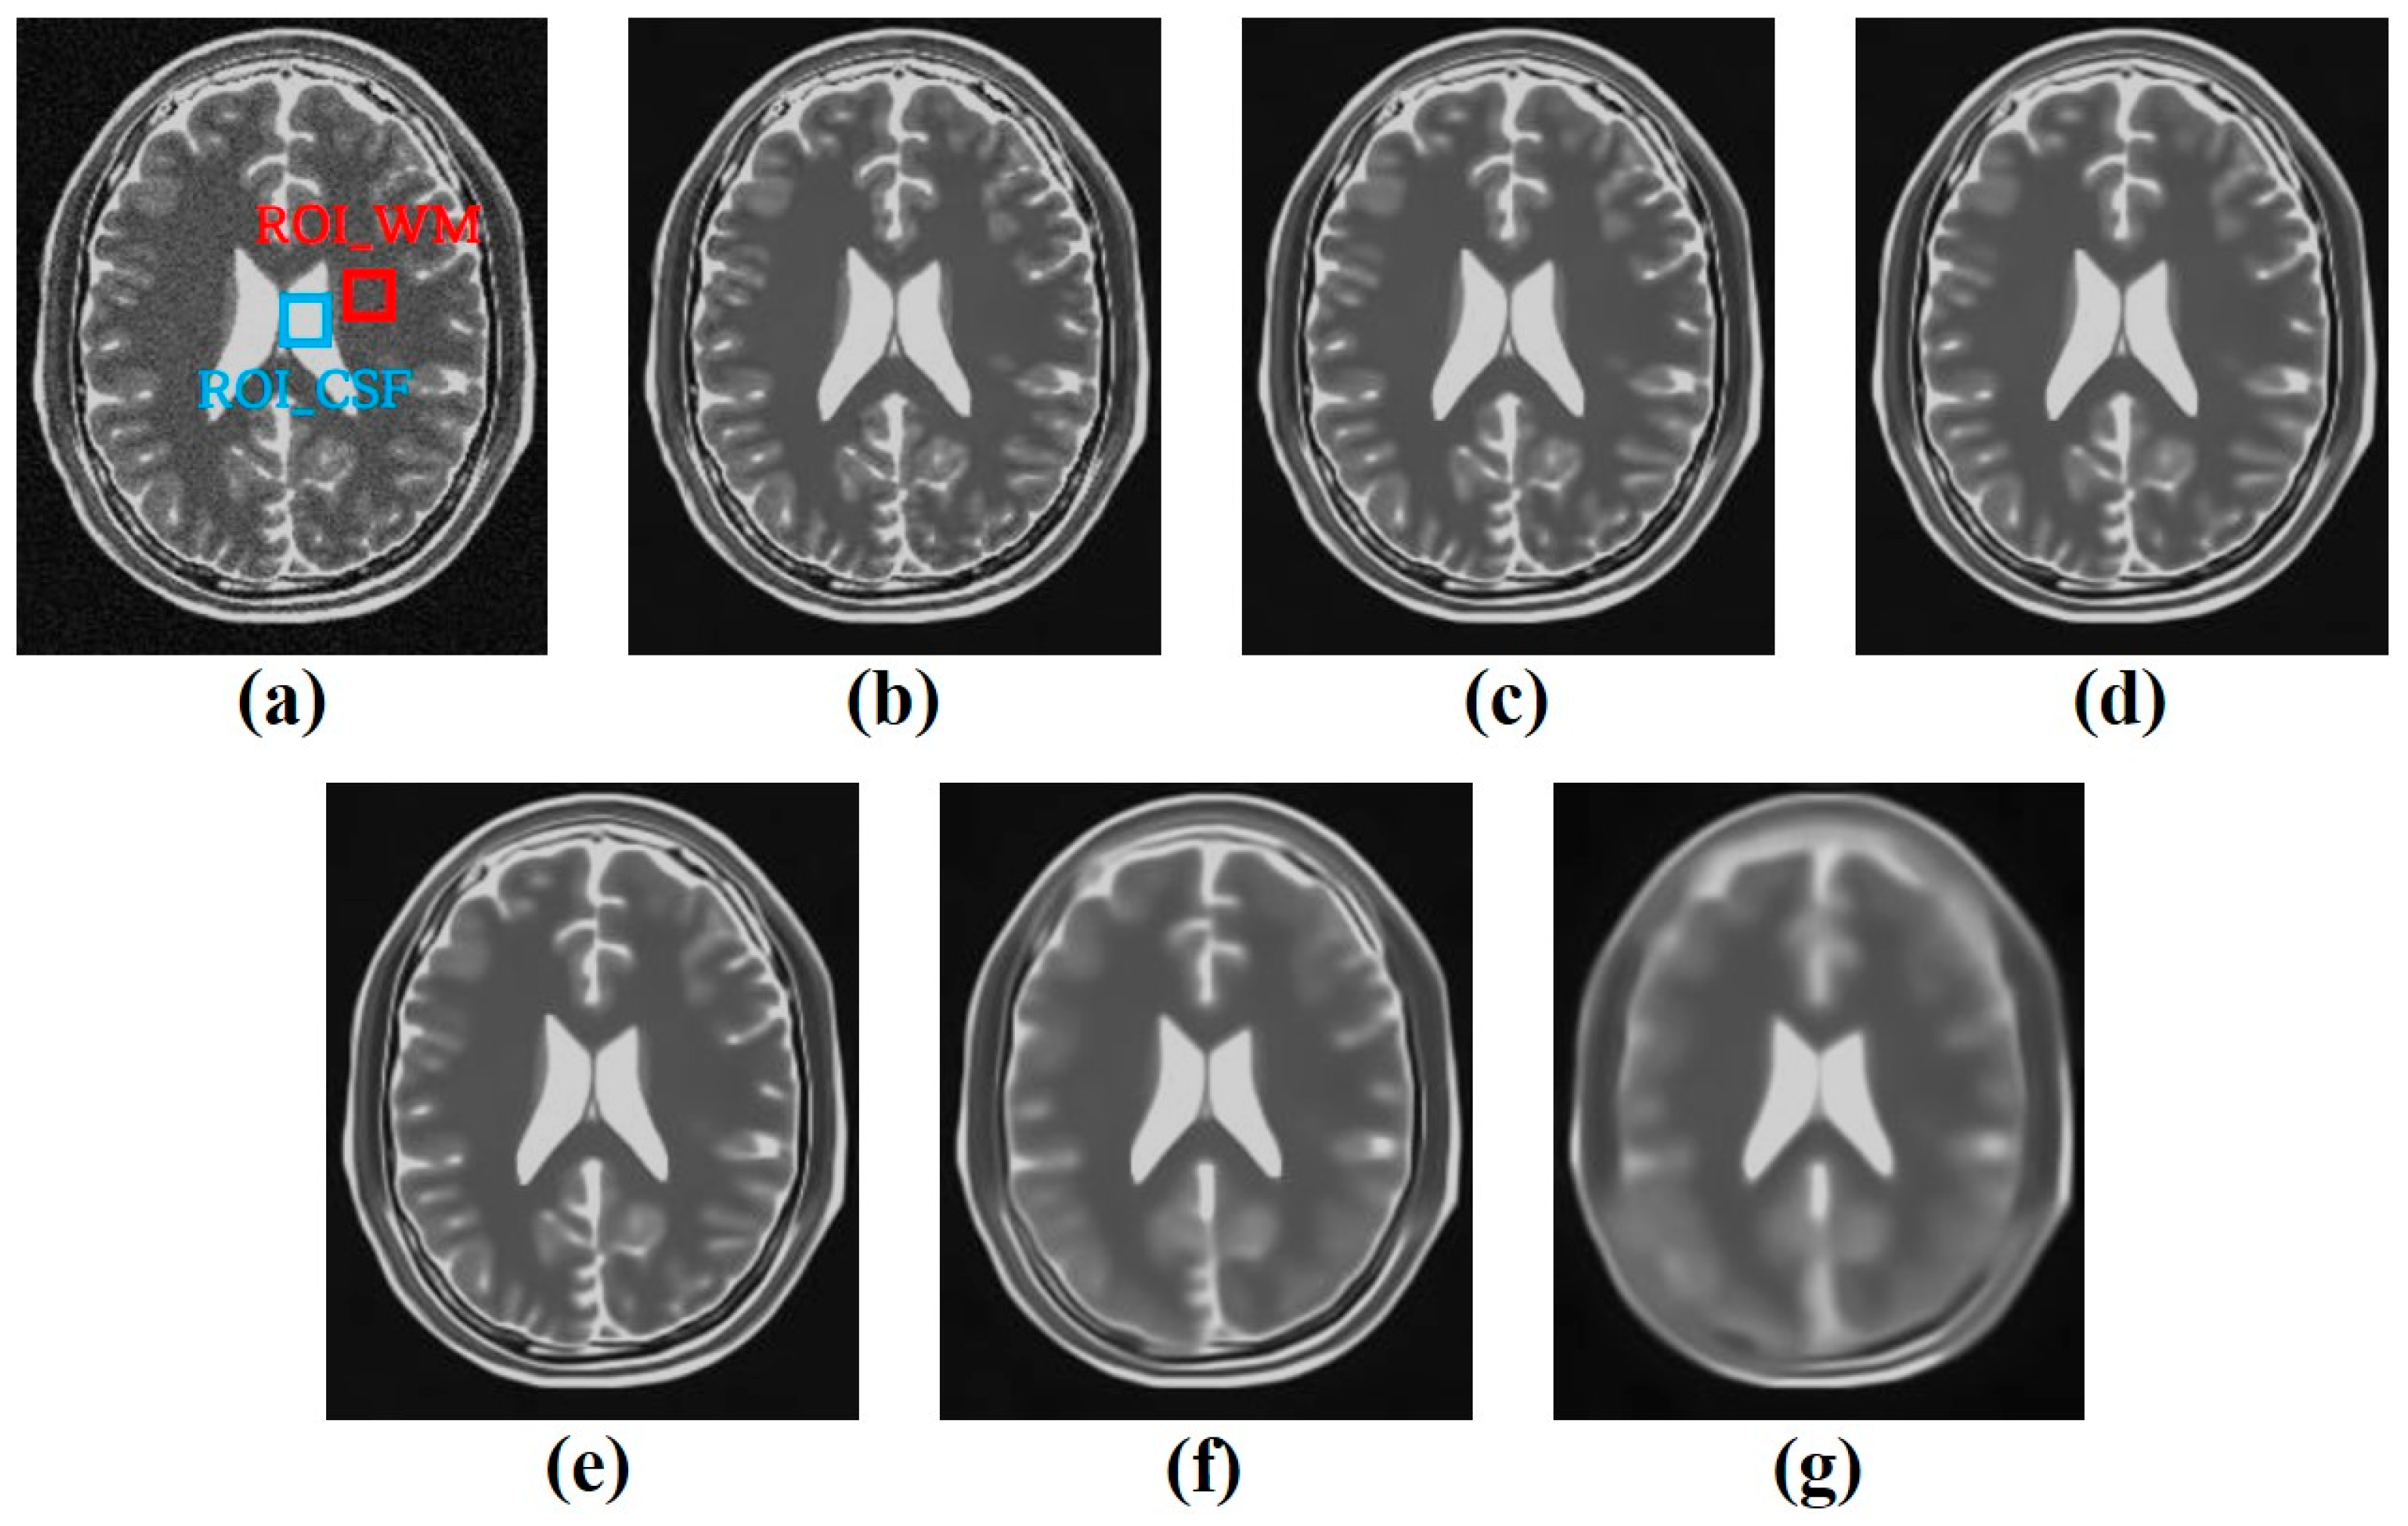

3.1. Simulation Study

3.2. Clinical Study